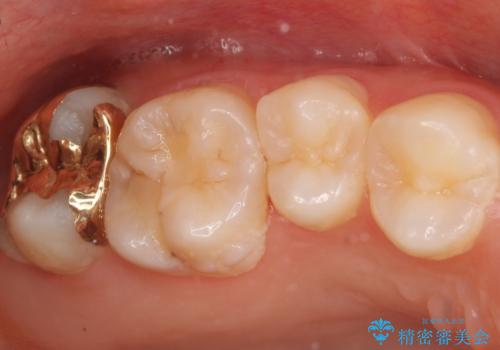

親知らずに面している歯の一部が深いところまでかなり脆くなってしまっていたため(広範囲での脱灰)、親知らずの抜歯後に精度の良いインレーを装着していきました。

- 右上7 ゴールドインレー 77,000円費用は治療当時の料金となります